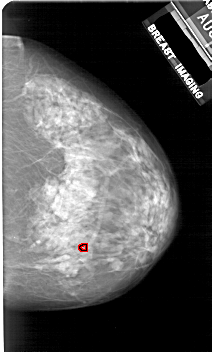

A_1924_1.LEFT_MLO

LEFT_MLO LINES 5386 PIXELS_PER_LINE 3856 BITS_PER_PIXEL 12 RESOLUTION 43.5 NON_OVERLAY